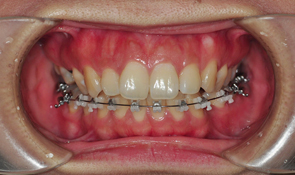

도착후 전체적인 점검을 하고 기존에 걸어 놓았던 와이어를 꺼냈습니다. 우와웅 한달밖에 안됫는데도 와이어에서 시간의 흔적이

보인다는... 양치질 더욱 열심히 해야겠다는 생각이 들었어요

와이어를 꺼낼때느 뭔가 시원한 느낌이 들더라구요 해체하는 기분 ㅋㅋㅋㅋ 와이어 없을때 얼른 사진 하나 찍었어요 쿄쿄

뭔가 2% 부족한 느낌,,